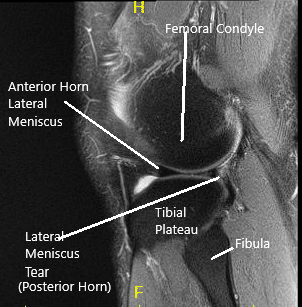

MRI of the left knee suggested a  lateral meniscal tear.. There was mild  partial-thickness cartilage loss along the central trochlear groove and in the lateral compartment.

MRI of the Knee in coronal and sagittal sections